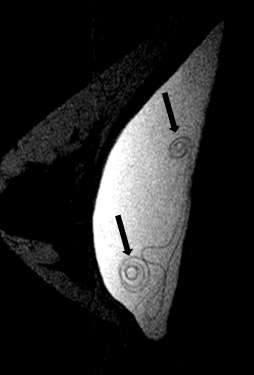

Intracapsular rupture with focal collapse of the outer shell will result in the “keyhole sign”, also referred to as the “noose sign”. This sign appears as a focal invagination of the hypointense outer shell where the two membranes do not touch. Similarly, the “teardrop sign” appears as a focal invagination of the hypointense outer shell containing a droplet of hyperintense extravasated silicone gel with the partial apposition of the two membranes13 (Figure 5).